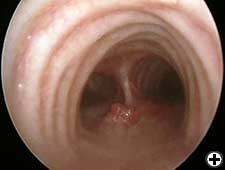

Cardiac function is assessed based on a physical examination, electrocardiography, and transthoracic echocardiography in all patients. Radiological work-up includes standard chest X-ray, total body CT-scan, bone scintigraphy and PET scan, where indicated. All patients should be submitted to rigid bronchoscopy (Figure 3) and sometimes to virtual bronchoscopy (Figure 4) to precisely assess the extent of invasion and the required resection. Mediastinoscopy (in case of malignant tumors), performed at the time of planned resection, may be useful to discover potentially involved lymph nodes, to evaluate the mediastinal and extraluminal spread of the neoplasm and to dissect the pretracheal plane, enhancing the mobility of upper trachea and reducing the risk of recurrent laryngeal nerve injury.